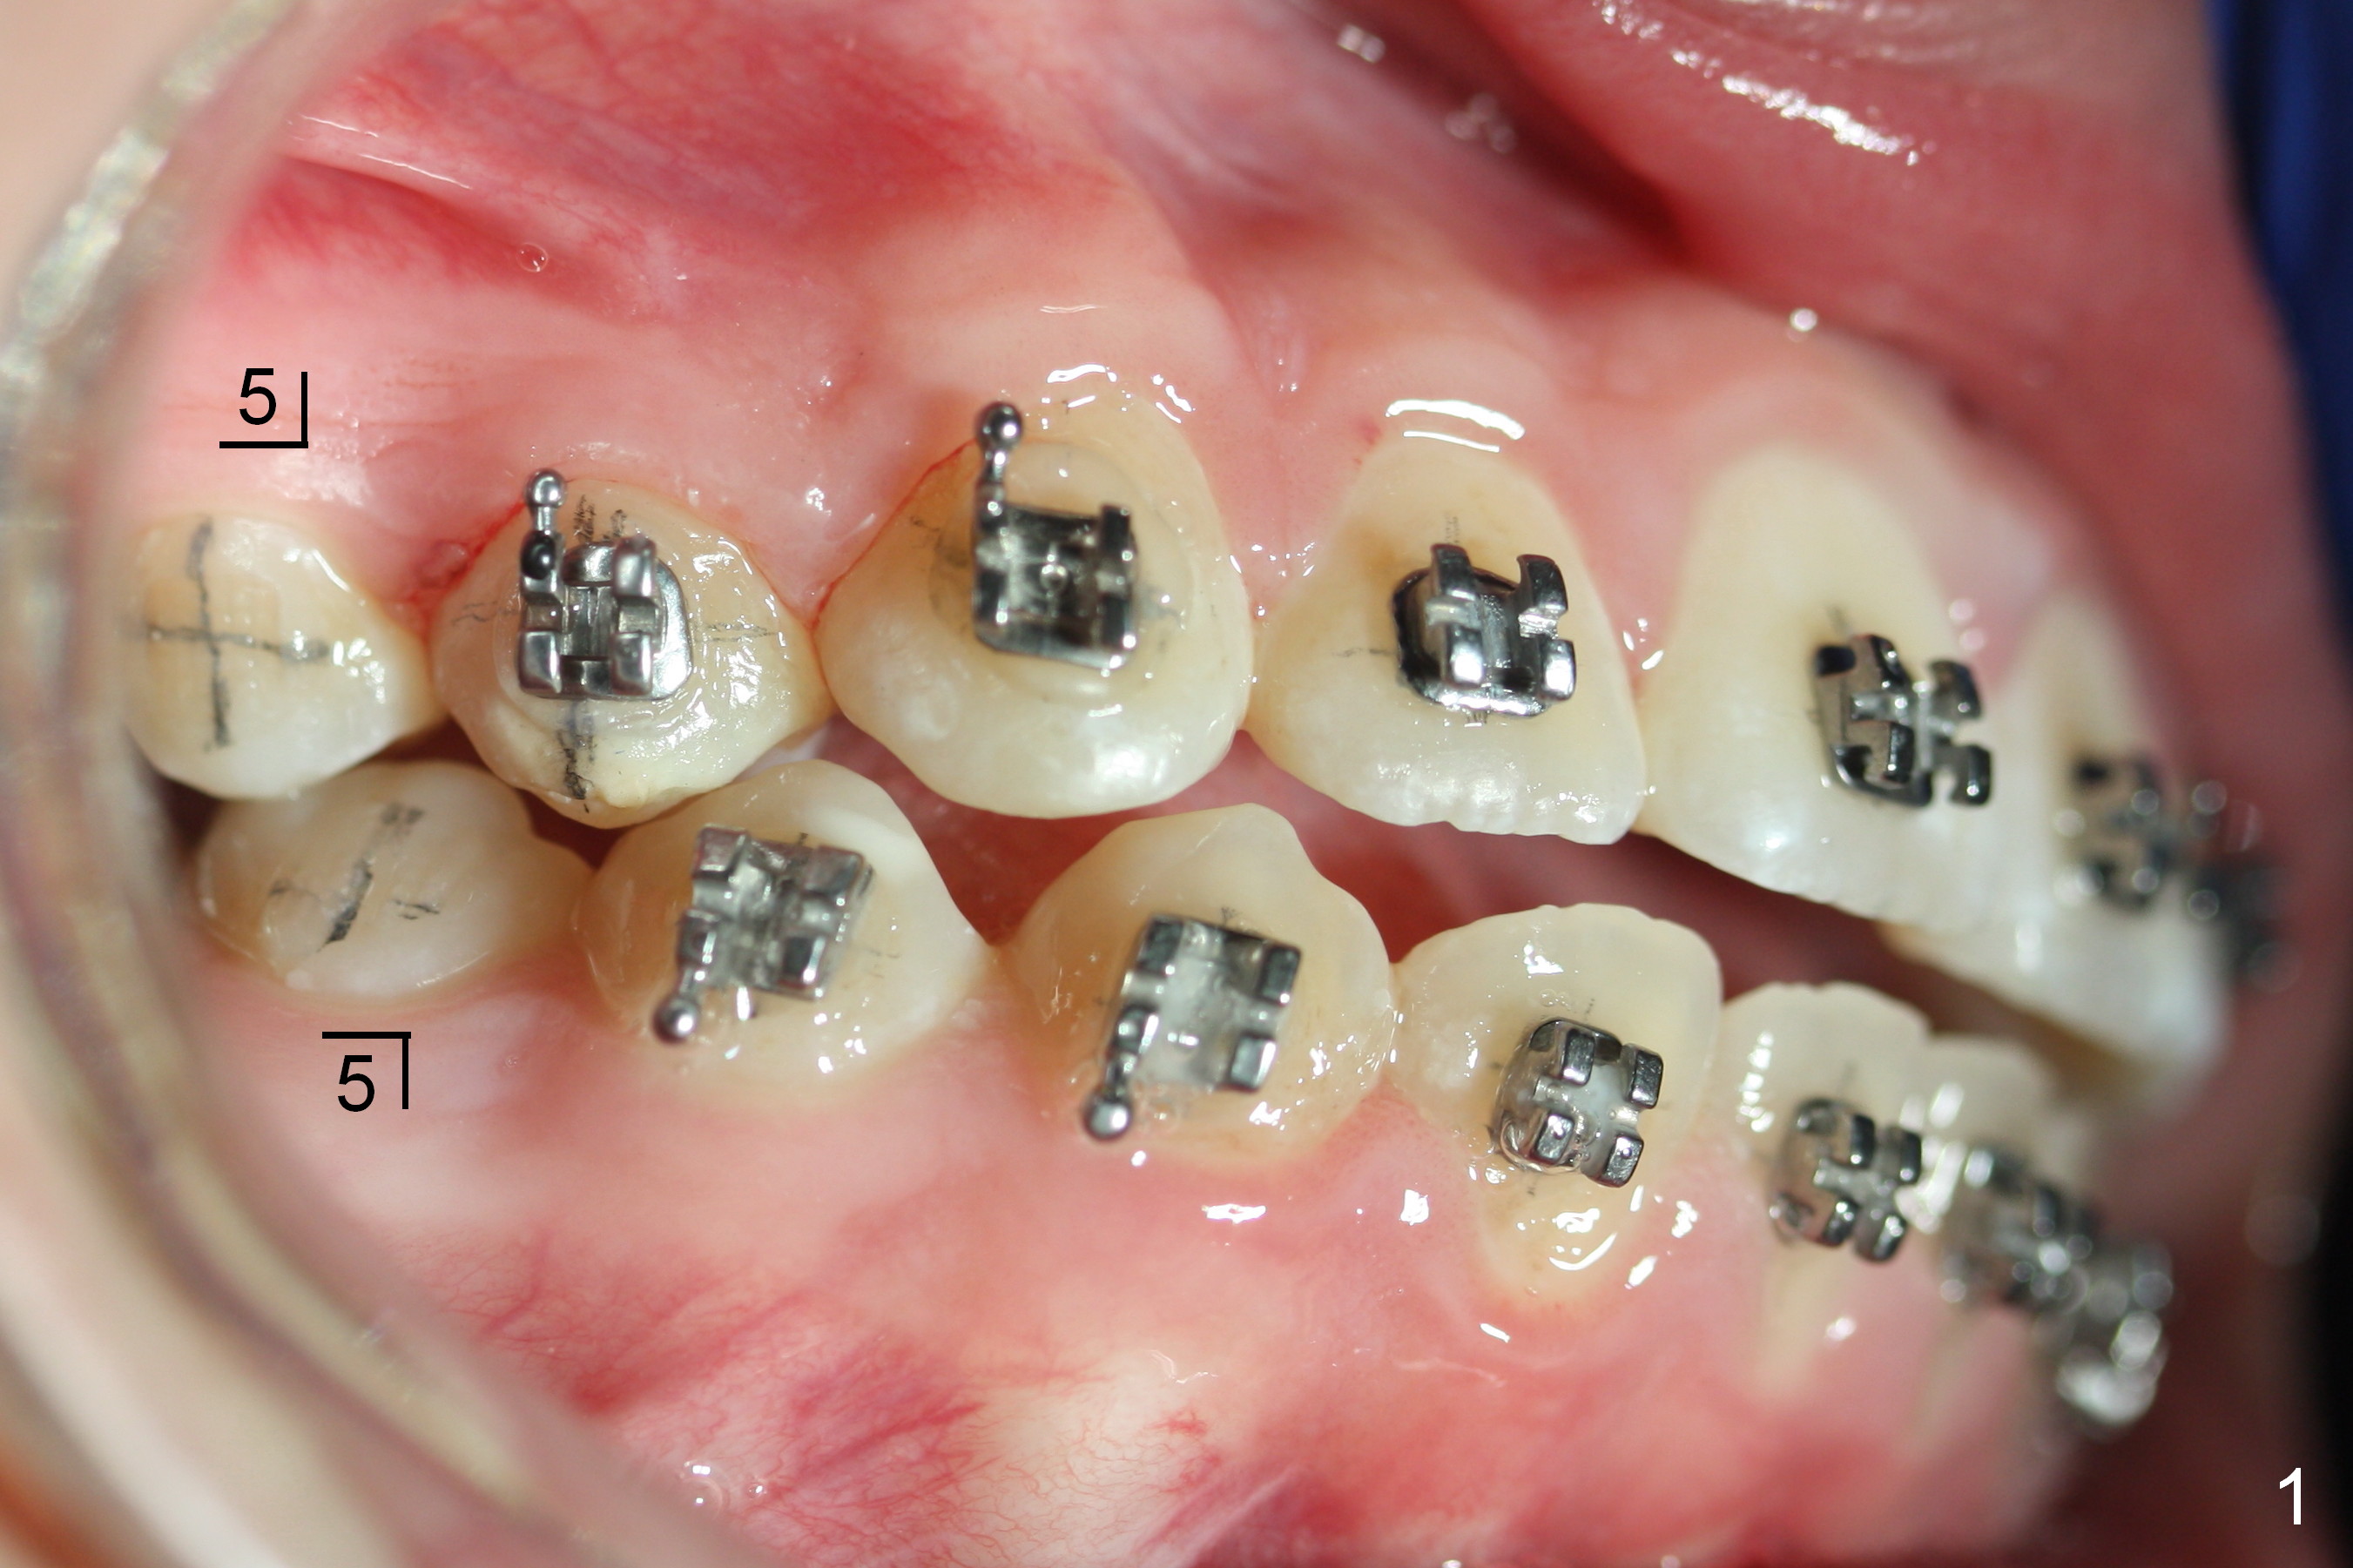

A 15-year-old Spanish female has been in orthodontic treatment for 2 years 3 months (1 2 3). Facial profile is convex (same as preop (Fig.5-8)) with anterior open bite (Fig.1,2). Four bicuspid extraction is considered. Since brackets of the 2nd bicuspids have been lost (Fig.1,2) and there are pathologies associated with the lower ones (Fig.3,4), all of the 2nd bicuspids have been extracted. Plan is to retract the 1st bicuspids, canines and incisors sequentially. How to close the anterior open bite?

Approximately 4.5 months of power chains between 4s and 6s buccally, U4s contact U6s with rotation (Fig.13,14), while L4s have 1-2 mm to be distalized (Fig.15,16). With placement of lingual buttons on U4s and power chains lingually, the rotation should be corrected. The rotation wedges were placed with ligature wire on the left in the last visit. The patient returns 3 weeks later.